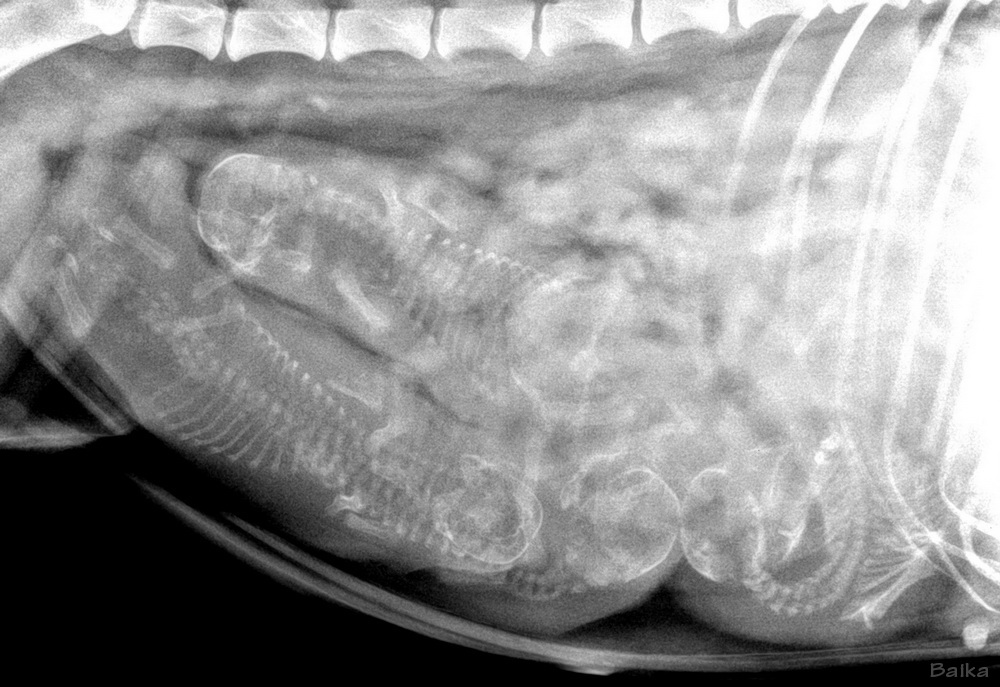

Entwicklung der einzelnen Welpen: Felix Carus Shadow Filou Freddy Shadow Flora Freya Night

allgemeine Bilder des Wurfes: Gruppenbilder